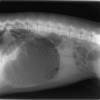

最近来院した4歳のチベタリアン・コッカー・スパニエル。腹腔内の大きな嚢胞(約10×20㎝)が確認できる。手術で摘出した嚢胞は異常に膨大した出所不明の組織で、現在病理検索中。稀な症例

最近来院した4歳のチベタリアン・コッカー・スパニエル。腹腔内の大きな嚢胞(約10×20㎝)が確認できる。手術で摘出した嚢胞は異常に膨大した出所不明の組織で、現在病理検索中。稀な症例 よく見るとバリウムに縁どられているのはねずみです。猫が同居しており、猫ジャラシのねずみのおもちゃです。腸閉塞を起こしていたのはこのねずみでした。開腹手術するも腸を切開せず

よく見るとバリウムに縁どられているのはねずみです。猫が同居しており、猫ジャラシのねずみのおもちゃです。腸閉塞を起こしていたのはこのねずみでした。開腹手術するも腸を切開せず